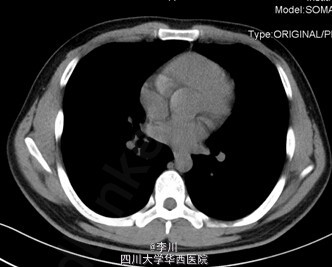

心肺腹查体无特殊。双侧手掌及足潮湿明显。胸部CT无特殊异常。